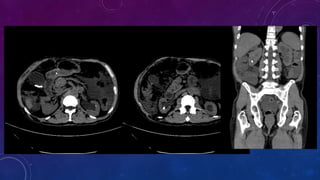

CHRONIC CALCIFIC PANCREATITIS

• #13 Chronic calcific pancreatitis